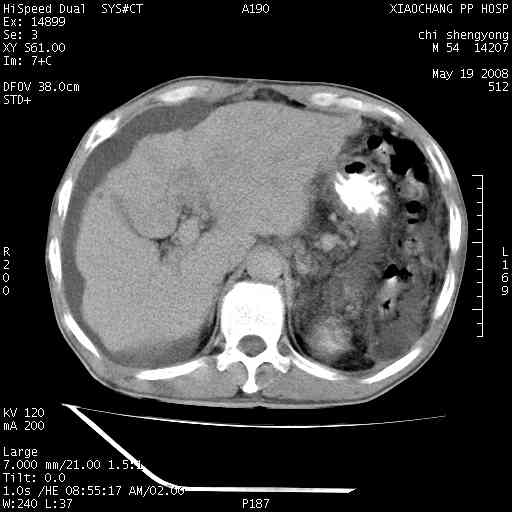

以下是引用zjzjr在2008-5-21 10:52:00的发言:[br]肝左叶巨块型肝癌伴门静脉左支瘤栓形成.肝硬化、腹水,胃底静脉曲张,脾术后改变。

以下是引用随光逐影在2008-5-21 16:20:00的发言:[br]1)肝左叶肝癌伴门静脉左支瘤栓形成,腹膜后淋巴结转移。2)肝硬化、腹水、胃底静脉曲张。3)胆囊炎。4)脾脏缺如,为切除术后所致。